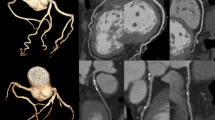

ROC curve analysis

C-statistics of kurtosis revealed the area under the curve (AUC) is 0.727 (95%CI 0.665–0.784). The best cut-off of kurtosis for ACS was 2.74, with an accuracy of 74.0%, sensitivity of 55.8%, and specificity of 83.12%. For the median HU, the AUC is 0.66 (95%CI 0.595–0.721), with the best cut-off of median HU set at 196, an accuracy of 68.0%, a sensitivity of 48.1%, and a specificity of 77.9%. The AUC of kurtosis and median HU are both significantly higher than that of the standard AS (AUC = 0.502), and the number of TRF (AUC = 0.537) (Kurtosis vs. AS and TRF p < 0.001, p < 0.001, respectively; median HU vs. AS and TRF p = 0.03, p = 0.04, respectively). (Fig. 2) Testing these cutoffs on a separate 1:2 matched cohort revealed that kurtosis has an accuracy of 64%, a sensitivity of 60%, and a specificity of 65%, whereas median HU has an accuracy of 55%, a sensitivity of 30%, and specificity of 55%. Combining kurtosis and median HU using a discriminant function, we found that using the following formula: (0.0217*median HU – 1.9059*Kurtosis), with a cutoff of 0 resulted in a sensitivity of 49.4% and a specificity of 90.9% with an accuracy of 77.1%.

Receiver operating characteristic curves of Agatston score, traditional risk factors, kurtosis of attenuation, and median of attenuation in the prediction of ACS in subjects with low CAC burden

Receiver operating characteristic (ROC) curves of Agatston score (AS), Agatston score, traditional risk factors, kurtosis of attenuation, and median of attenuation. Kurtosis (p < 0.001) and attenuation median were significantly superior to TRF and AS. There was no significant difference between kurtosis and median attenuation

In Fig. 2, the AUC of AS and TRF is close to 0.5, indicating that the study successfully removed the confounding effect of AS and TRF by propensity matching. In this scenario, a median CAC attenuation with a cut-off at 196 yielded a better AUC (AUC = 0.66, OR = 0.969) compared to AS and TRF, and kurtosis of attenuation with a cut-off value of 2.74 was able to deliver an even better AUC in all subjects (AUC = 0.727, OR = 18.7). The predictive ability of kurtosis alone is comparable to that of a composite radiomics-based score derived from a retrospective cohort study[17].